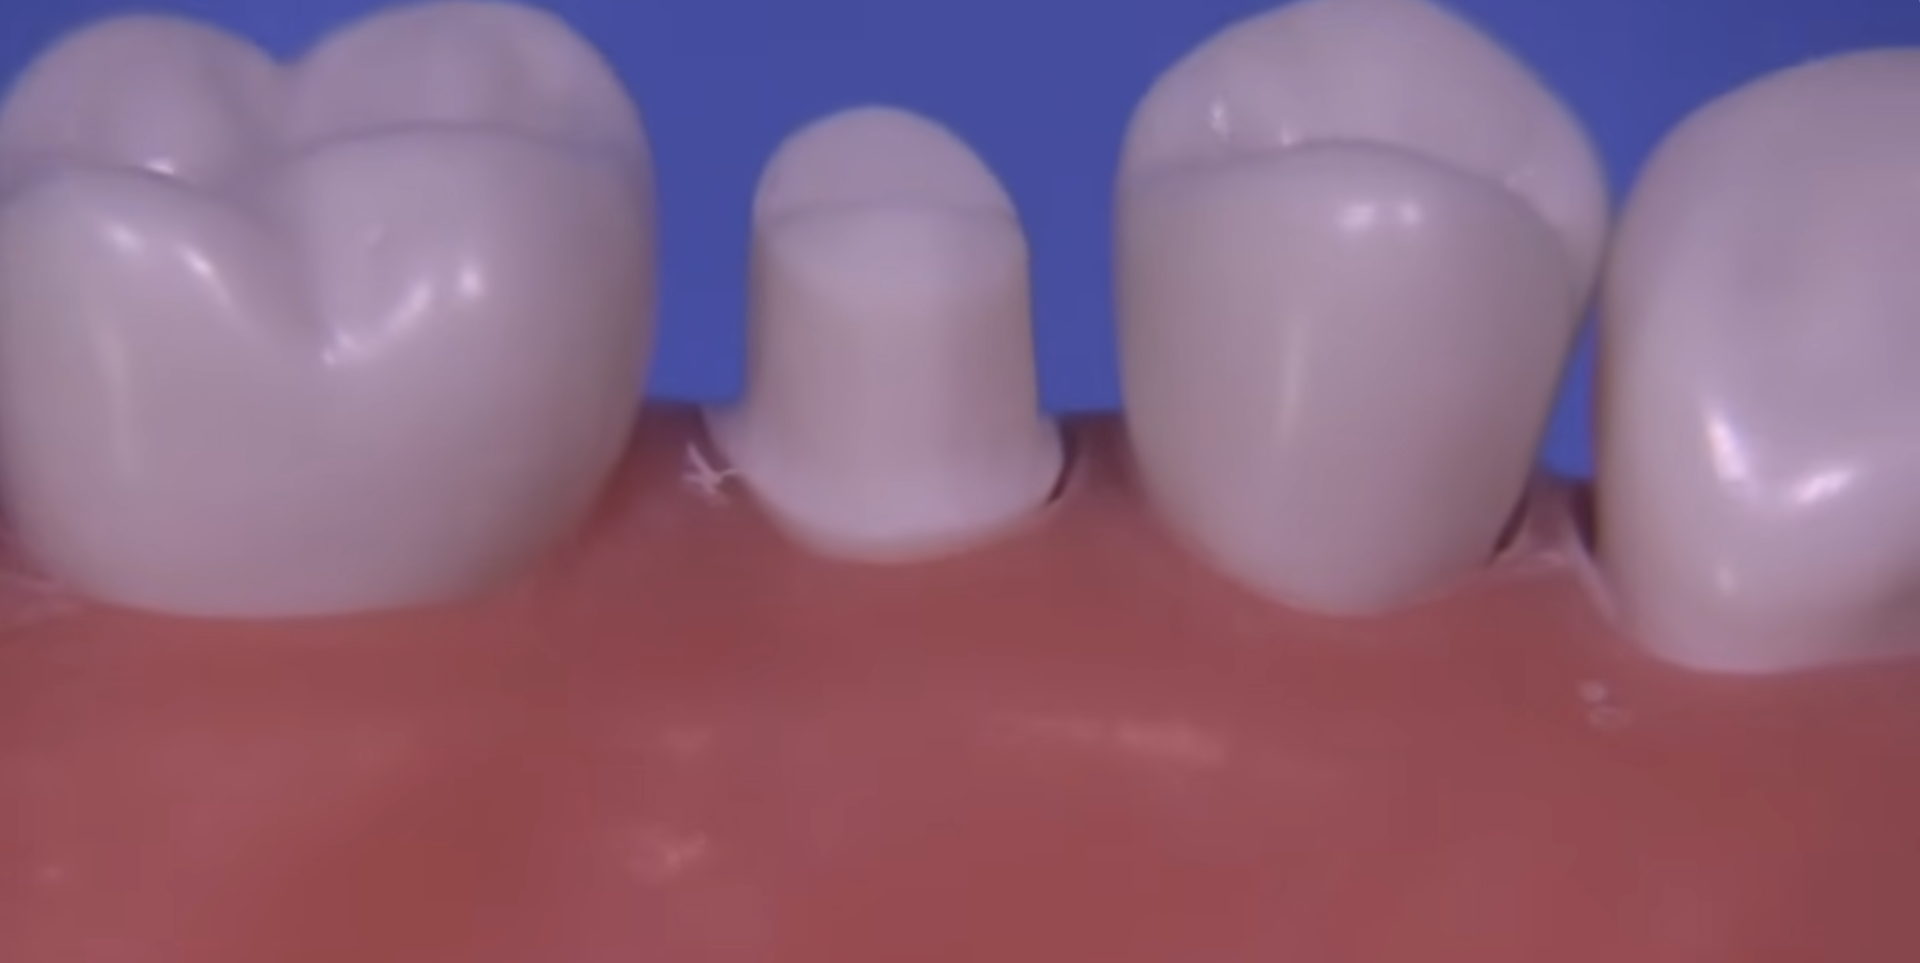

For at lave en tandkrone kræver det, at tanden får en form som en trafikkegle. Kronen sidder så som en kegle oven på anden kegle med cement. Det betyder at der skal slibes rigtigt meget af den tand som bærer kronen – ca 60-75%.

Billederne er herunder er taget fra en undervisningsvideo, hvor en plastictand slibes til af en ekspert.